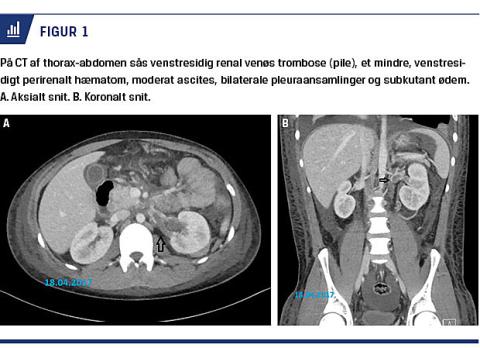

efter fem dage med et vægttab på 3 kg og et albuminniveau på 12 g/l. Han blev genindlagt tre dage efter på mistanke om appendicitis med bælteformede stærke mavesmerter i øvre abdomen med udstråling til nedre kvadranter uden feber, kvalme, opkastning eller ændring i afføringen. Ved en objektiv undersøgelse fandt man, at han var begyndende peritonal. Paraklinisk var der et leukocytniveau på 26,7 × 109/l og et C-reaktivt proteinniveau på 4,9 mg/l. En CT af thorax-abdomen viste venstresidig renal venøs trombose (RVT), et mindre venstresidigt perirenalt hæmatom (følger efter

nyrebiopsi), moderat ascites, bilaterale pleuraansamlinger og subkutant ødem (Figur 1). Han blev samme dag overflyttet til et nyremedicinsk afsnit på et andet hospital til videre behandling. Her foretog man hverken trombolyse grundet en nybiopteret nyre og øget